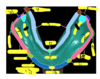

Adequate Mesial - Distal Width:

________is needed to place implant : ______ minimum between adjacent teeth

Adequate Mesial - Distal Width:

Interradicular space is needed to place implant : 7 mm minimum between adjacent teeth

ID green

palatine aponeurosis (tensor veli palatini, levator veli palatini) palatopharyngeus, palatoglossus, and musculas uvale